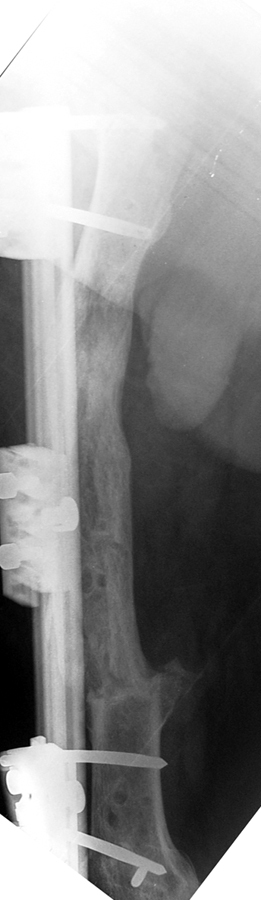

Vaka 1